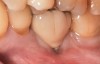

Problem: Two adjacent implants are located in the central–lateral incisor positions, and the patient has a high smile line along with loss of inter-implant papilla and midfacial recession around both implants (Figure 29 and Figure 30).33-38

Solution: Decoronate the implants by placing cover screws over both of them. Two weeks later, place connective tissue grafts and/or dermis allograft over the cover screws to augment soft-tissue volume. Repeat the mucosal grafting procedure as needed. Expose one of the implants in a more favorable prosthodontic position, and then create an ovate pontic over the submerged implant with a cantilevered fixed dental prosthesis design (Figure 31).

Fig 29. Two adjacent implants placed in the esthetic zone can lead to loss of the interdental papilla and a negative outcome for a patient with a high smile line.

Fig 30. The intraoral view of the loss of the interdental papilla between teeth Nos. 9 and 10.

Fig 31. The solution to the problem in Figure 29 and Figure 30 was to decoronate the implants, augment the site, uncover 1 implant, and place a cantilevered cement-retained 2-unit implant-supported fixed dental prosthesis.